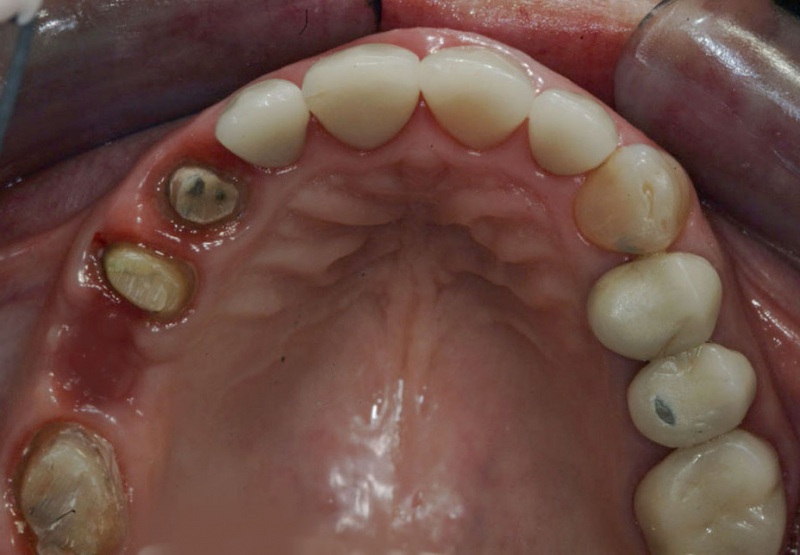

- Examination & Treatment Plan

- Periodontal Exam (Appointment 1)